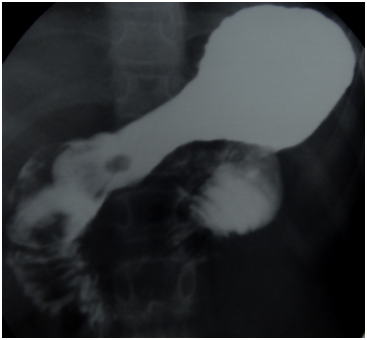

A 12year old female patient presented in paediatric emmergency with history of upper gastrointestinal bleeding for 2days with severe anaemia and associated mucocutaneous pigmentation. Two units of blood transfusion was given to the patient. Upper GI Endoscopy revealed well defined polyps in pyloric antrum, larger one prolapsing into pyloric antrum from duodenal bulb suggestive of Peutz Jeghers Hamartomatous polyp (Figure 1). On single contrast barium meal examination a small well defined lobuted filling defect is found in pyloric antrum of stomach. Another large filling defect is seen in duodenal bulb causing expansion of it and protruding into antropyloric region (Figure 2).

Figure 2 On single contrast barium meal examination a large filling defect is seen in duodenal bulb which is protruding into antropyloric region. Another small well defined lobuted filling defect is also found in pyloric antrum of stomach.